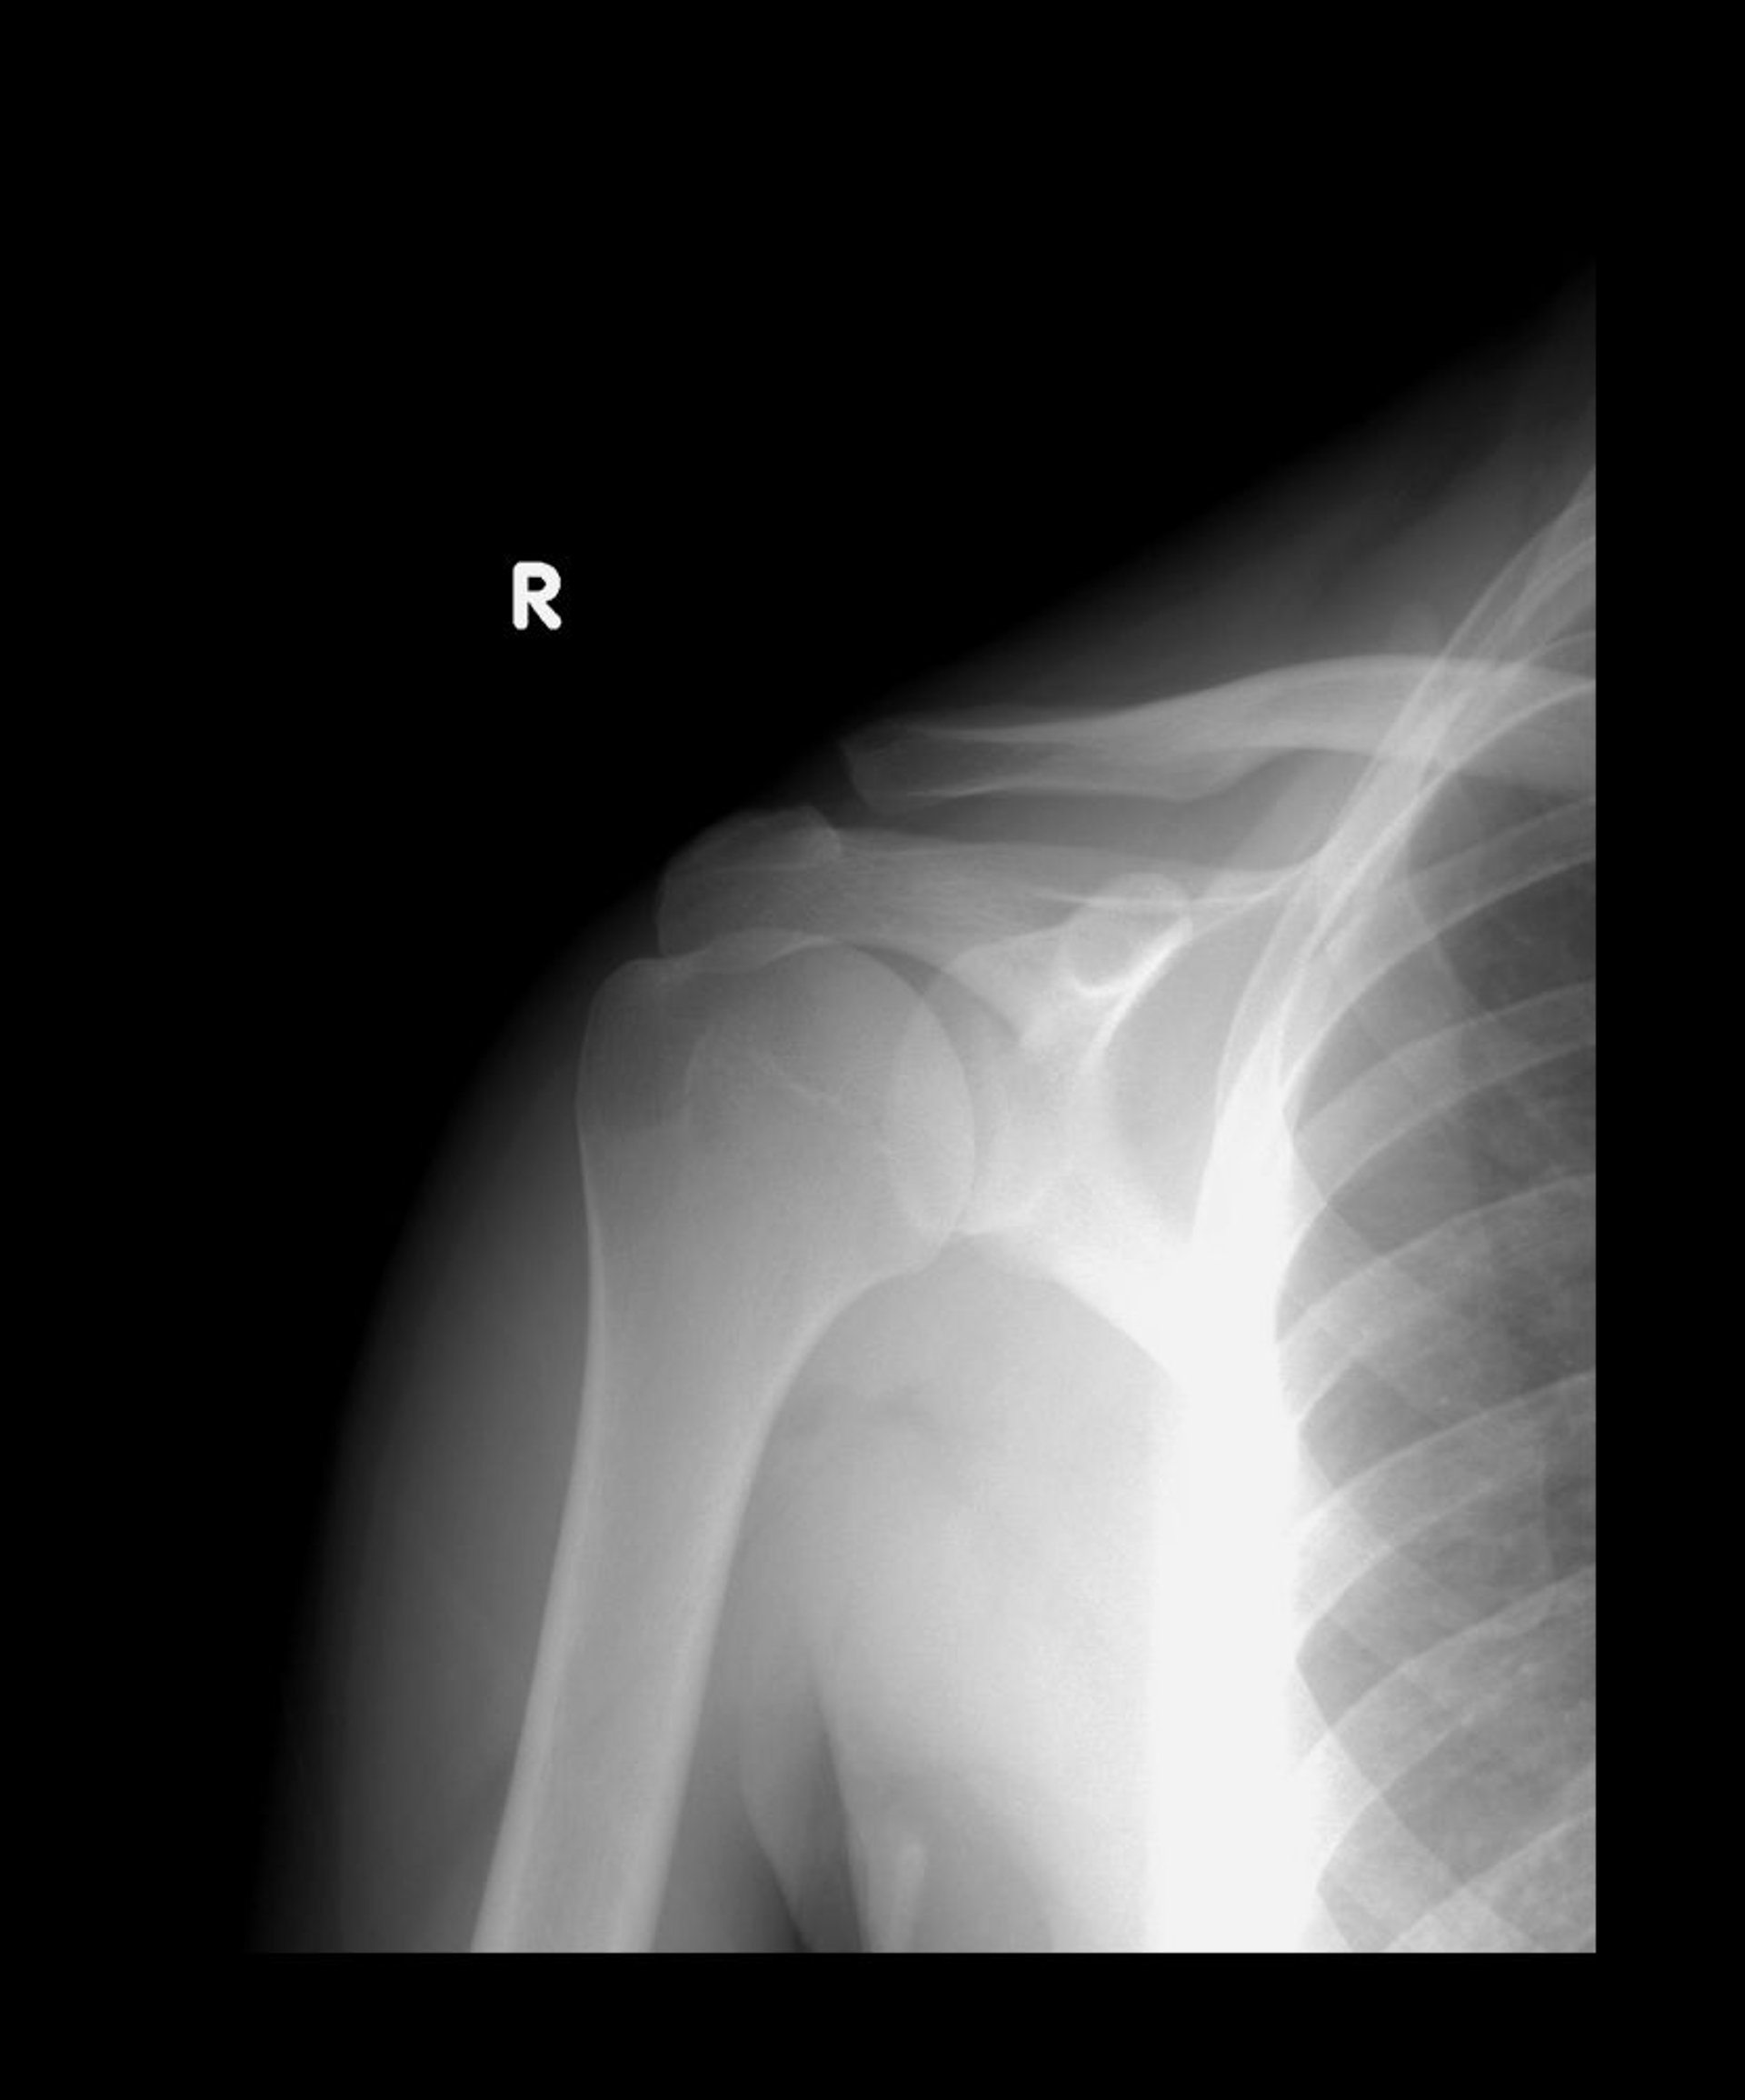

Verstauchung des Akromioklavikulargelenks

Normalerweise stehen die unteren Enden des Akromions und der Clavicula in einer Linie. In dieser Röntgenaufnahme ist das Schlüsselbein nach oben verschoben, aber die beiden Knochen überlappen immer noch, was auf eine Subluxation vom Typ II hindeutet.